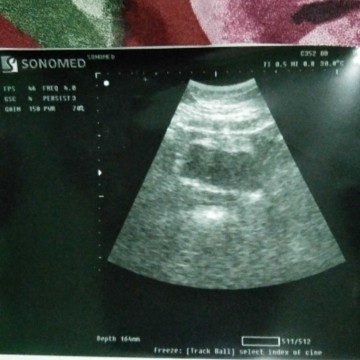

Apakah benar juka sudah gambar seperti ini sedang pembuahan??

Baca lagiiya udh di tanya dengan detail.. saya baru di bidan blm ke dokter. nah katanya ini masih penebalan. tapi, saya yaqin klw ni udh proses gtu cma msh umuran di bawah 1 minggu gtu.. dan yg saya rasa, mual, kram ringan, suka gampang capek dan kerasa ngeganjal di area perut bawah itu yg dirasa.

semoga aja doa dan ikhtiar kami allah mengijabkan🤲 karna selama ini blm pernah ngerasain hal sepertii ini. dan saya kurang faham karna masih 3 bulan pernikahan🙏 terimakasih untuk supprotnya bunda² sholehah🥰